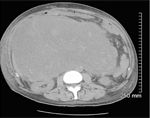

FIGURE 1

CT Scan

-Computed tomographic image demonstrating the patient's advanced gastrointestinal stromal tumor.